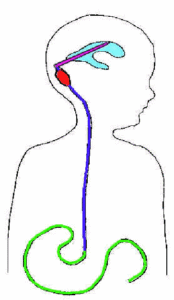

Bei fortbestehender Fehlregulation der Liquordynamik ist die Versorgung des Patienten mit einem speziellen Ventil-Schlauchsystem (Shunt) unumgänglich. Ein solcher Shunt verläuft unter der Haut vom Ventrikel in ein anderes Körperkompartiment (meist in den Bauchraum). Der überschüssige Liquor wird von dort in die Blutbahn aufgenommen und gelangt damit letztendlich genau dort hin, wo er auch auf natürlichem Wege resorbiert wird.

Das Ventil regelt, ab welchem Druck abfließt. Alle derzeit auf dem Weltmarkt vorhandenen Ventile sind rein mechanisch gesteuert. Die meisten haben einen voreingestellten Solldruck, bei einigen lässt sich der Druck von außen stufenweise einstellen. Ist der Druck im Kopf höher als der Ventilsolldruck, öffnet sich das Ventil und Liquor kann abfließen. Wenn allerdings der Druck im Bauchraum höher ist, kann sich das Ventil nicht öffnen und es fließt trotz des zu hohen Druckes im Kopf kein Liquor. Manchmal ist es daher erforderlich, den Liquor über eine große Vene in das Herz abzuleiten, zum Beispiel bei stark übergewichtigen Patienten, die längere Zeit liegen müssen.

Der Shunt, das heißt die Gesamtheit des Schlauchsystems und des Ventils, wird in Vollnarkose unter der Haut verlegt. Die Operation dauert in der Regel weniger als 1 Stunde. Mit speziellen OP-Instrumenten ist es möglich, die Shunts minimal-invasiv zu verlegen. Es sind lediglich 3 - 4 kleine Hautschnitte notwendig.